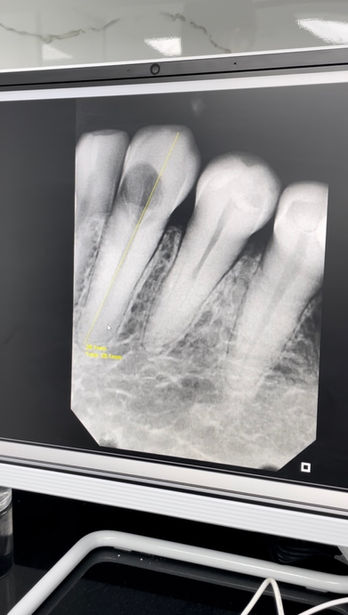

Contamos con micromotores rotatorios y localizadores de ápice que permiten una limpieza y conformación precisa de los conductos. Además, nuestro Equipo de Radiografía Intraoral Digital con Proyección de Imágenes Inmediatas nos brinda diagnósticos rápidos y exactos con mínima exposición a la radiación.

Galería de Soluciones: Restaurando Sonrisas con Endodoncia

Descubre cómo en Face Clinic salvamos dientes y restauramos la salud bucal de nuestros pacientes a través de la endodoncia.

Iniciamos con una exploración clínica detallada y radiografías digitales (con nuestro equipo de radiografía intraoral digital) para diagnosticar con exactitud el estado de la pulpa y la infección.